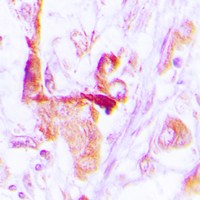

IHC (Immunohiostchemistry)

(Dilution: WB: (1/500 - 1/1000), IH (1/100 - 1/200), IF/IC (1/100 - 1/500)Immunohistochemical analysis of EEF2 staining in human lung cancer formalin fixed paraffin embedded tissue section. The section was pre-treated using heat mediated antigen retrieval with sodium citrate buffer (pH 6.0). The section was then incubated with the antibody at room temperature and detected using an HRP conjugated compact polymer system. DAB was used as the chromogen. The section was then counterstained with haematoxylin and mounted with DPX.)